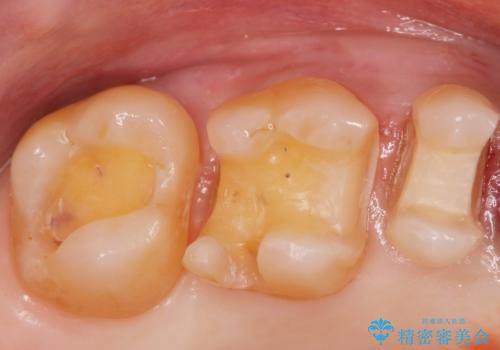

- メタルインレーやりかえ希望の患者様です。

拡大鏡下でメタル、う蝕の除去を行いe-maxインレー(セラミックインレー)で治療しました。

適合の良いe-maxインレーが入りました。

銀の詰め物に比べてセラミックインレーは虫歯の再発のリスクが少なくなります。